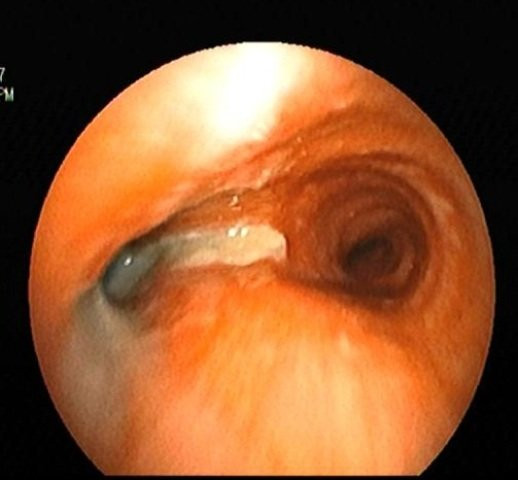

Các bác sĩ đã tiến hành soi phế quản, kết quả soi và kiểm soát đường thở phát hiện trong phổi bệnh nhân có rất nhiều đờm mủ bên phổi trái, đồng thời thấy có dị vật kích thước 1cm trong phế quản thùy dưới của bên trái.

Hình ảnh dị vật được gắp ra từ phổi của bệnh nhân.

ThS. BS Nguyễn Văn Giang cho biết, ngay sau khi phát hiện dị vật đã nhanh chóng tiến hành nội soi gắp thành công dị vật nguy hiểm trong phổi của bệnh nhân này. Kết quả giải phẫu dị vật được kết luận là một mô liên kết xơ cơ rất hi hữu và khó xác định là vật thể gì. Tuy nhiên, khi khai thác lại bệnh nhân Đặng Thị Nh cho biết, trước đó 6 tuần bệnh nhân có đi ăn lẩu và vô ý bị sặc. Do vậy dị vật được xác nhận chính là miếng thịt chui vào phế quản bệnh nhân bị sặc trong khi ăn lẩu.